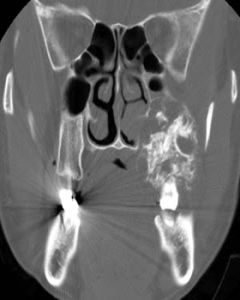

CT平掃時,囊腫為圓形或卵圓形,邊緣光滑。囊腫的密度與囊內容物有關,一般有兩種情況:多數表現為低密度,少數為等或高密度。前者與囊腫內容物是液態脂類物質和膽固醇有關,後者與囊內容物是角化物、出血和鈣化有關。增強CT上,囊壁可有輕度強化,囊液無增強。其內可見殘留的牙根或牙齒,可見間隔,骨皮質連續性可有中斷,周圍軟組織內可見膨脹。